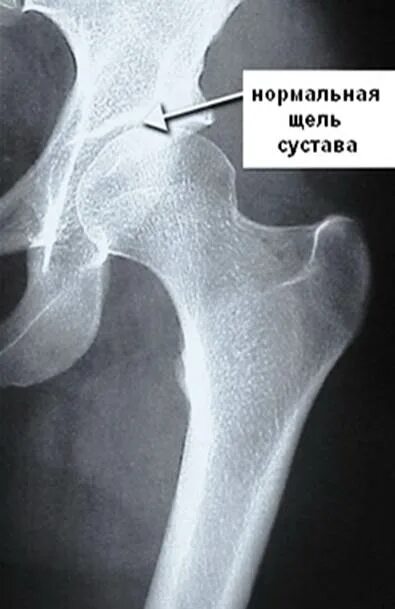

Суставная щель 3 3 мм